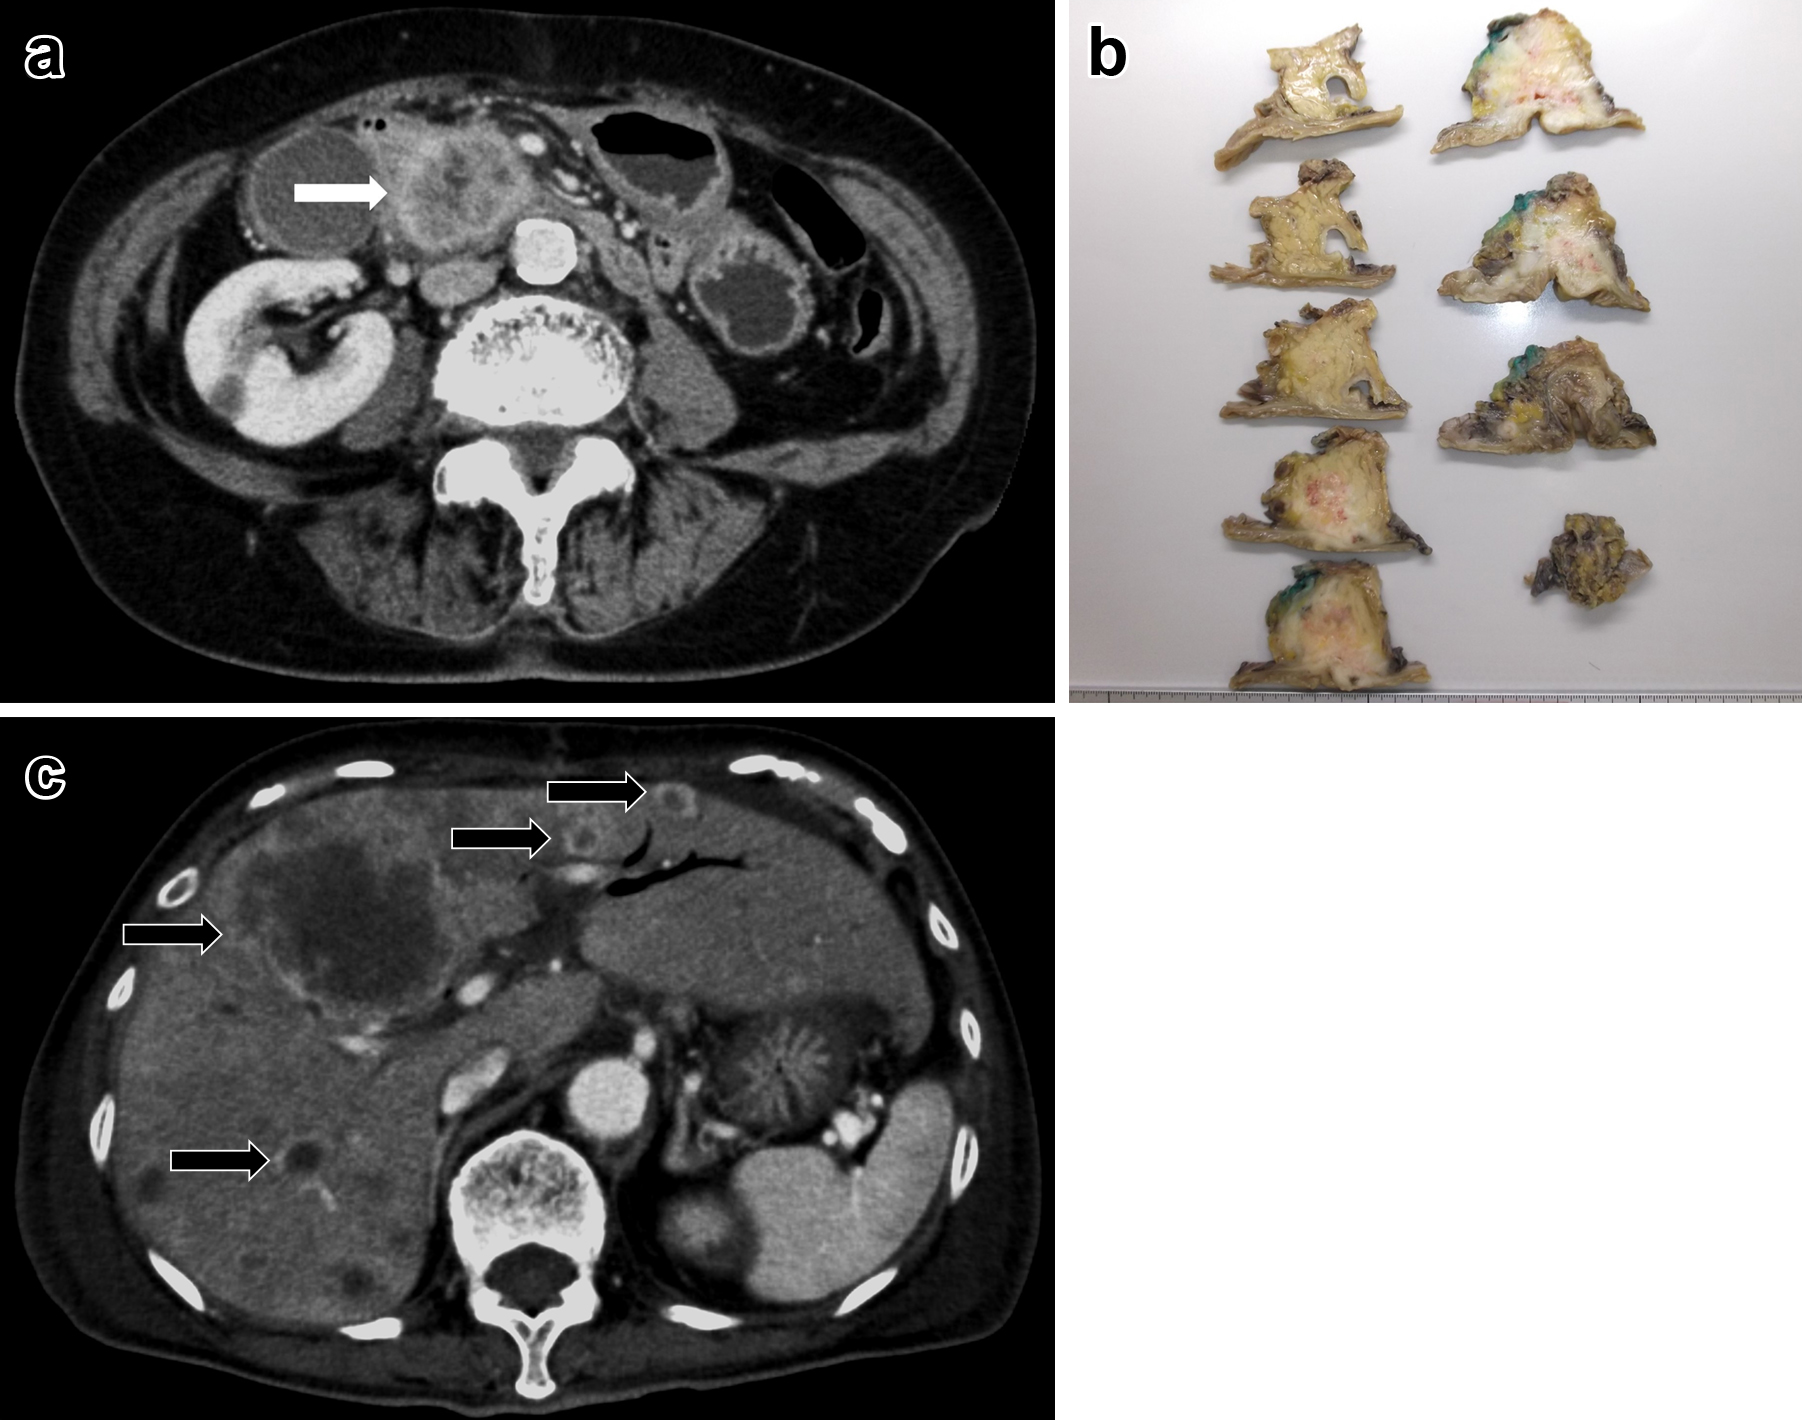

腹部造影CT所見:膵体部に25×16 mmの乏血性腫瘤を認めた.明らかな遠隔転移や周囲への浸潤は見られなかった(Fig. 1a).

a: Abdominal CT scan showed a low density mass 25 mm×16 mm in the body of the pancreas (white arrow). b: The tumor was solid, and it was 25 mm in diameter. c: Tumor induced stomach antrum penetration (white triangles).

経過:経過良好で術後30日目からS-1の内服を開始した.術後138日目に膵切除断端に局所再発を認め(Fig. 1c),S-1+gemcitabine(以下,GEMと略記)に変更したが,胃浸潤による出血のため,術後318日目に死亡した.

経過:膵液瘻(ISGPF grade B)を合併したが,術後35日目に退院した.術後47日目に多発肝転移を認め(Fig. 2c),S-1内服を開始したが,徐々に全身状態が悪化し,術後84日目に死亡した.

腹部造影CT所見:膵尾部に59×33 mmの乏血性腫瘤を認めた.明らかな遠隔転移や腫大リンパ節は認めなかった(Fig. 3a).

a: Abdominal CT scan showed a low density mass 59 mm×33 mm in the tail of the pancreas. b: The tumor was solid, and it was 40 mm in diameter. c: There were multiple liver metastases (black arrows) and local recurrence (white triangles).

経過:経過良好で,術後26日目からnab-paclitaxel+GEMを開始した.術後99日目に膵断端局所再発,多発肝転移を認め(Fig. 3c),cisplatin+GEMに変更したが,治療効果はprogressive diseaseであり,best supportive careの方針となって,術後307日目に死亡した.